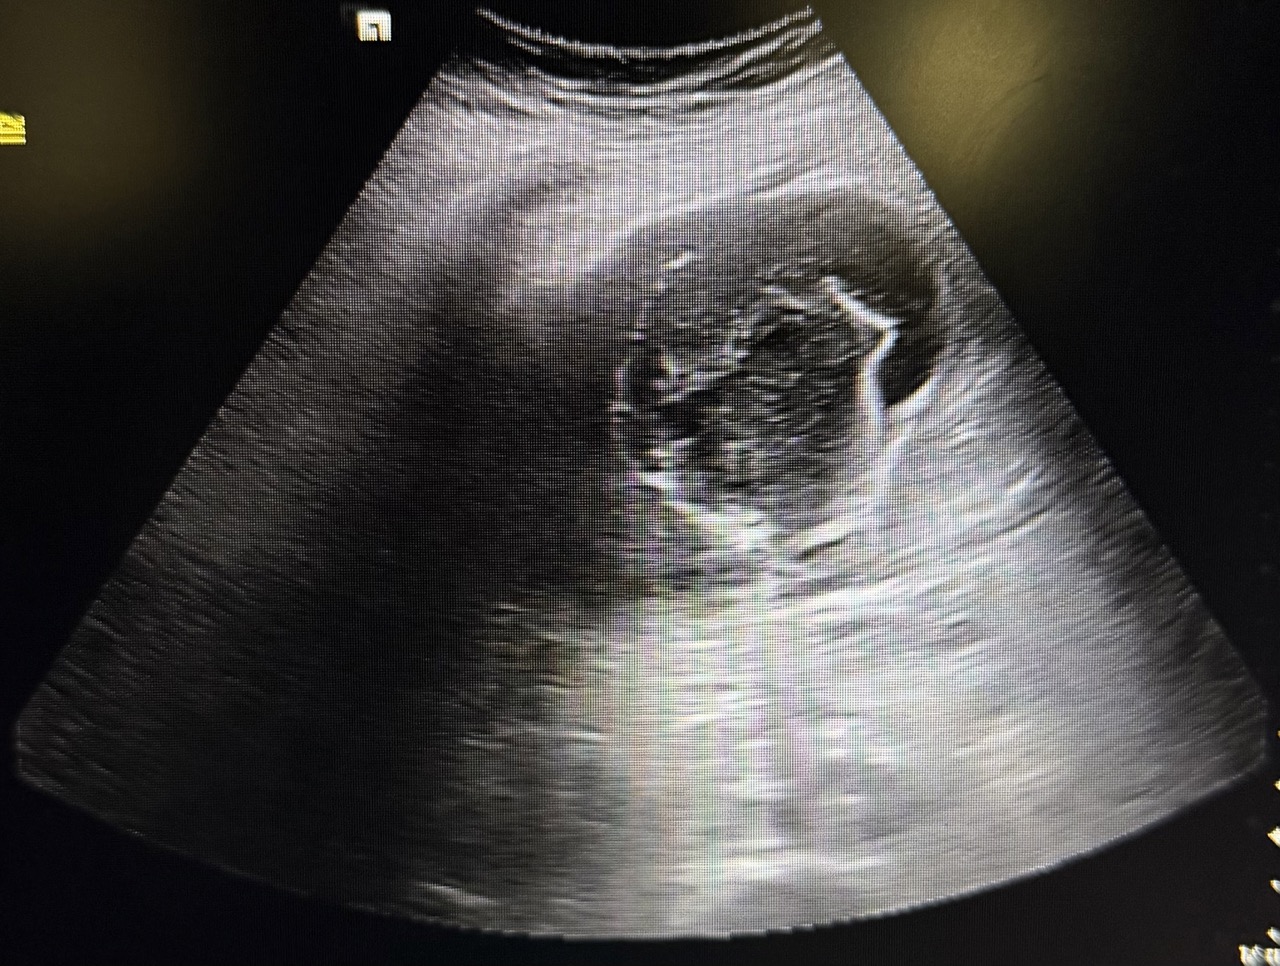

Ecografía en el centro de salud: Vesícula biliar con presencia de litiasis en su interior, distendida y engrosada. Murphy ecográfico positivo.

Desde el centro de salud, con la exploración y los hallazgos de ecografía nos orientó a colecistitis aguda litiásica por lo que se decidió traslado a urgencias para realización de analítica, ecografía por radiólogo y valoración por cirugía general.

La analítica junto con ecografía de urgencias coincidió con hallazgos observados en la ecografía del centro de salud, confirmando así colecistitis aguda evolucionada.